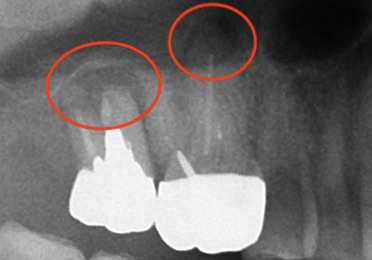

こちらはデンタルX線写真

赤丸の部分。根尖病巣によって黒くなっており、骨が溶けていて炎症が見られます。

揺れているのは一番奥でしたが。

両方根管治療した方が良さそうですね。

7番(一番左)にぶっといコアが‥😅